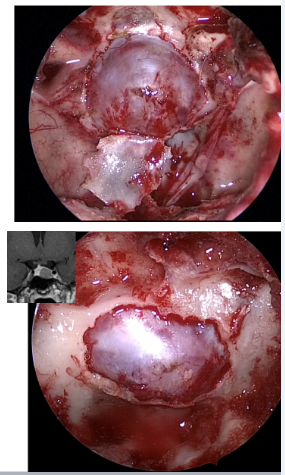

Post-operatively, the patient’s serum cortisol and ACTH were normalized as summarized in Table 1. Potassium levels were also normalized, and BP and blood sugar levels were controlled. Histological examination confirmed pituitary adenoma. The patient remained free from any symptoms suggestive of endocrinopathy at six months follow-up visit and no tumour recurrence (Fig 5).

Figure 5: Third postoperative month (follow-up visit), Coronal section of MRI showing complete resection of the pituitary tumour